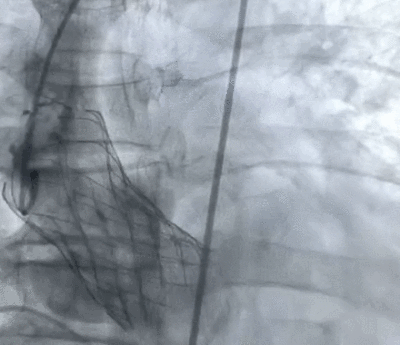

术后即刻:微量瓣周漏,舒张压明显改善至69mmHg。

术后造影